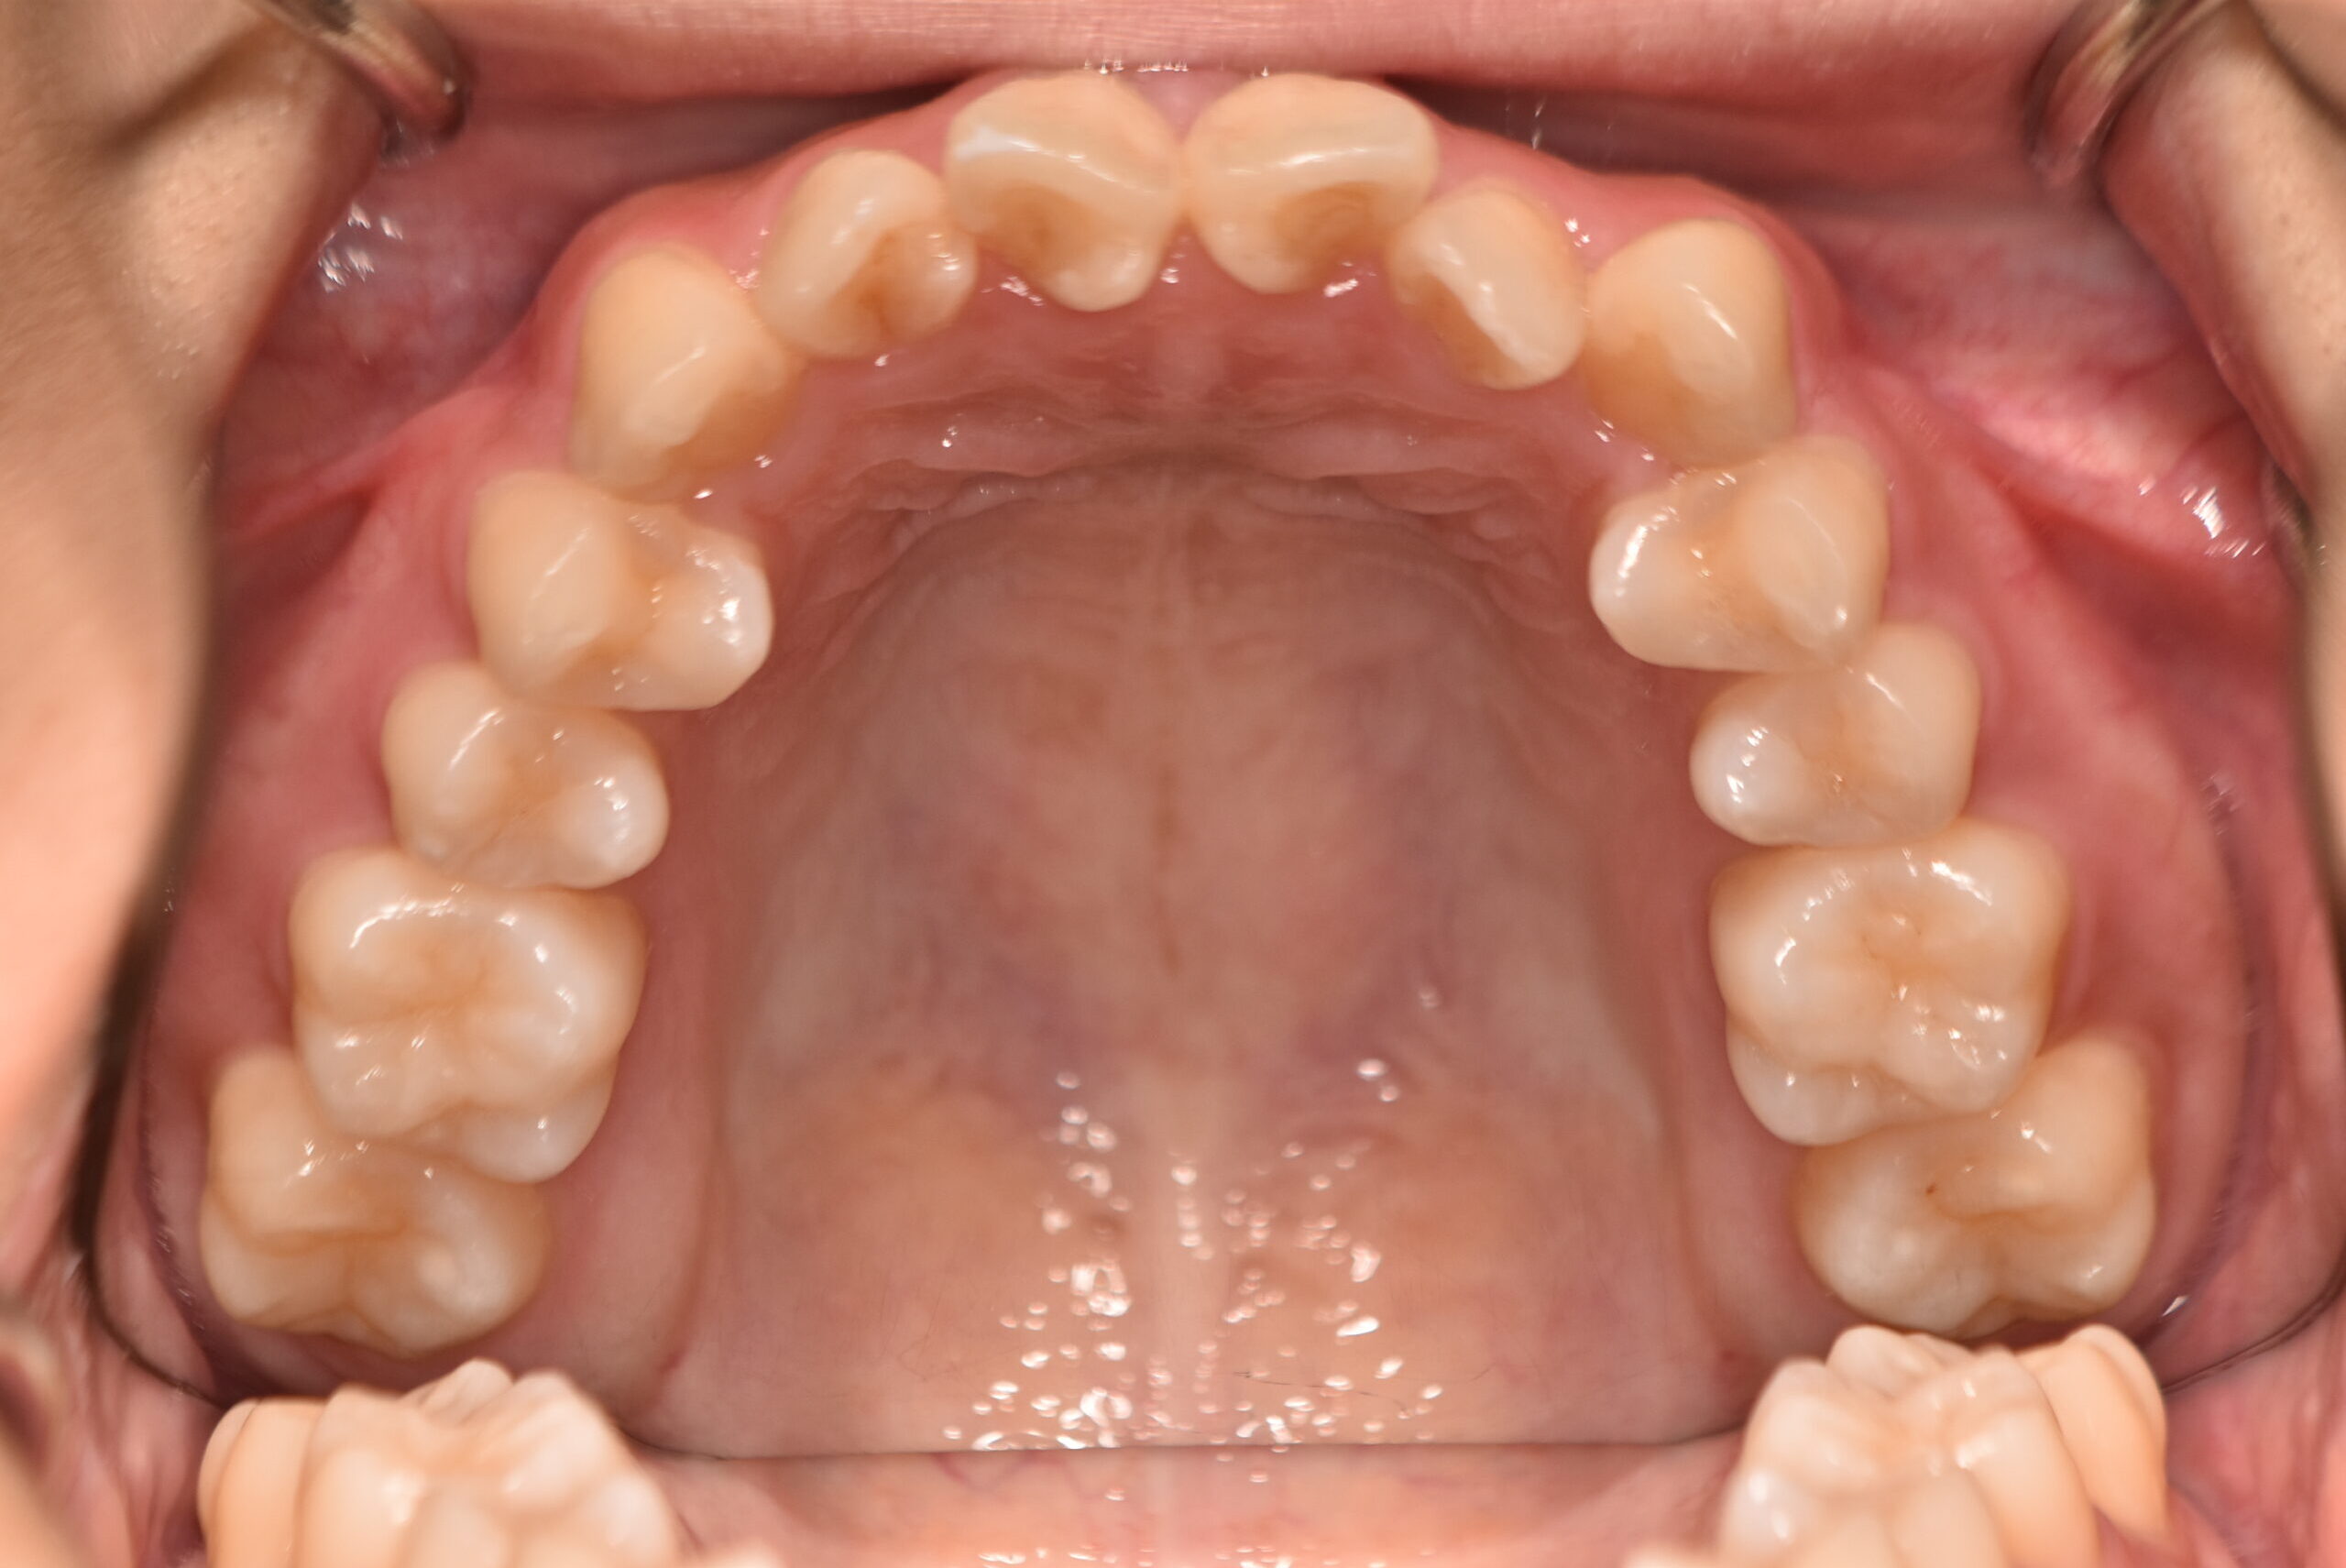

叢生(非抜歯)[2704]

動的治療終了時

症例 症例 症例 症例 症例

治療内容の詳細 初診時17歳の女性で、かみ合わせが悪く少しガタガタしていることをを気にされ来院されました。

検査の結果、上下顎叢生を伴うアングル1級不正咬合と診断しました。

治療としては、非抜歯の上、マウスピース型矯正装置(インビザライン)で歯の配列を行いました。

治療期間は、1年10ヶ月でした。